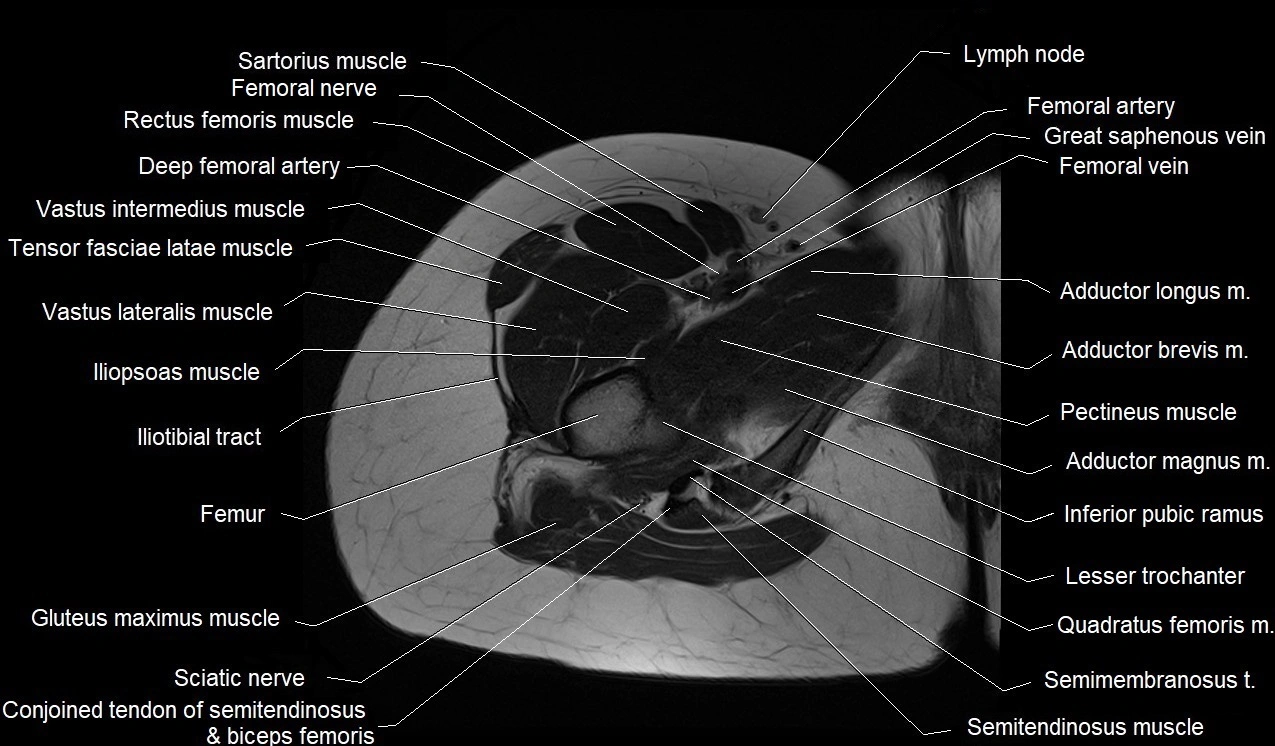

- Adductor brevis muscle

- Adductor longus muscle

- Adductor magnus muscle

- Femoral artery

- Femoral nerve

- Femoral vein

- Gluteus maximus muscle

- Iliopsoas muscle

- Iliotibial tract

- Inferior pubic ramus

- Lesser trochanter

- Pectineus muscle

- Quadratus femoris muscle

- Sartorius muscle

- Semimembranosus muscle

- Semitendinosus muscle

- Tensor fasciae latae muscle